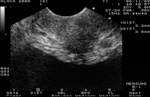

Диагностика скинеита (парауретрита)